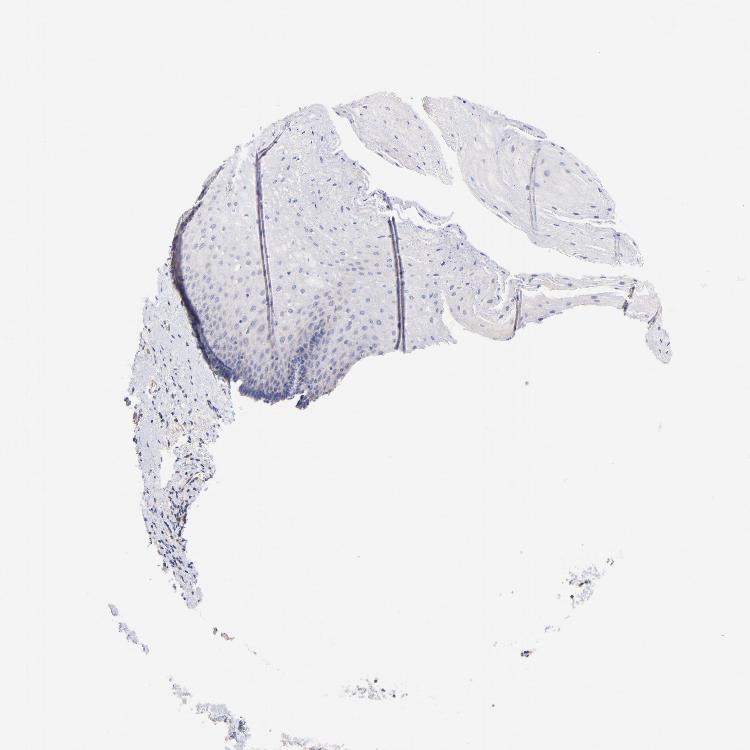

ESOPHAGUS - Antibody stainingi

Antibody staining in the annotated cell types in the current human tissue is reported as not detected, low, medium, or high, based on conventional immunohistochemistry profiling in selected tissues. This score is based on the combination of the staining intensity and fraction of stained cells.

Each image is clickable and will lead to virtual microscopy that enables deeper exploration of all samples and also displays staining intensity scores, fraction scores and subcellular localization as well as patient and tissue information for each sample.

Antibody HPA003246Antibody CAB008380

Squamous epithelial cells Not detectedNot detected